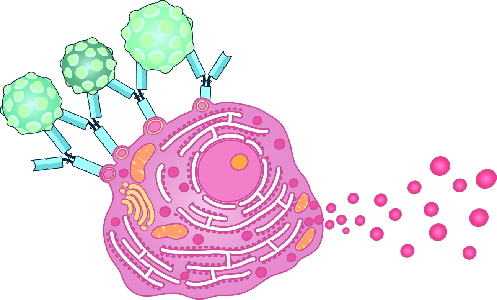

Detailreiche Fotografien aus der medizinischen Praxis ergänzen die Texte; moderne, genaue,

wissenschaftliche Zeichnungen geben Einblick in die Anatomie und die Funktion der Lunge und

anderer Organe.